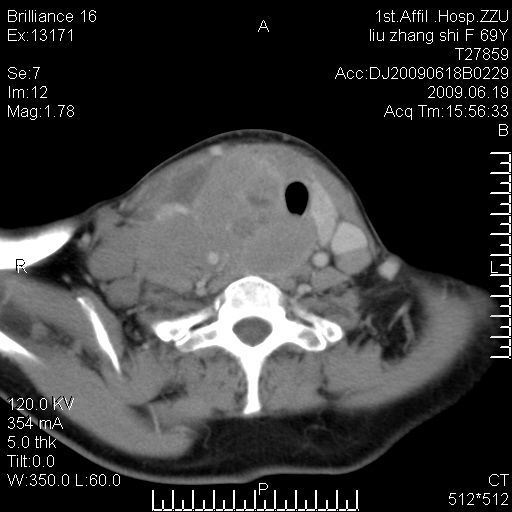

标题: CT26782:女,69岁,颈部占位,3天后公布病理结果。

【病理证实系列】女,69岁,颈部占位,有病理结果,3天后公布。(由于病例时间较久,临床资料不全,请网友见谅)本系列将有几百种常见、少见及罕见病例,均经病理证实。病例资料来自郑州大学第一附属医院。与网友共享,本人有空就发。

甲状腺癌并颈部淋巴结转移。感谢楼主的良苦用心,谢谢。

甲状腺癌并颈部淋巴结转移。

需与鼻咽癌鉴别!

支持甲状腺癌广泛侵及周围结构并颈部淋巴结转移。

鉴别:淋巴瘤、恶性神经源性病变、恶性纤维组织细胞瘤。

病理结果:颈部非霍奇金淋巴瘤。